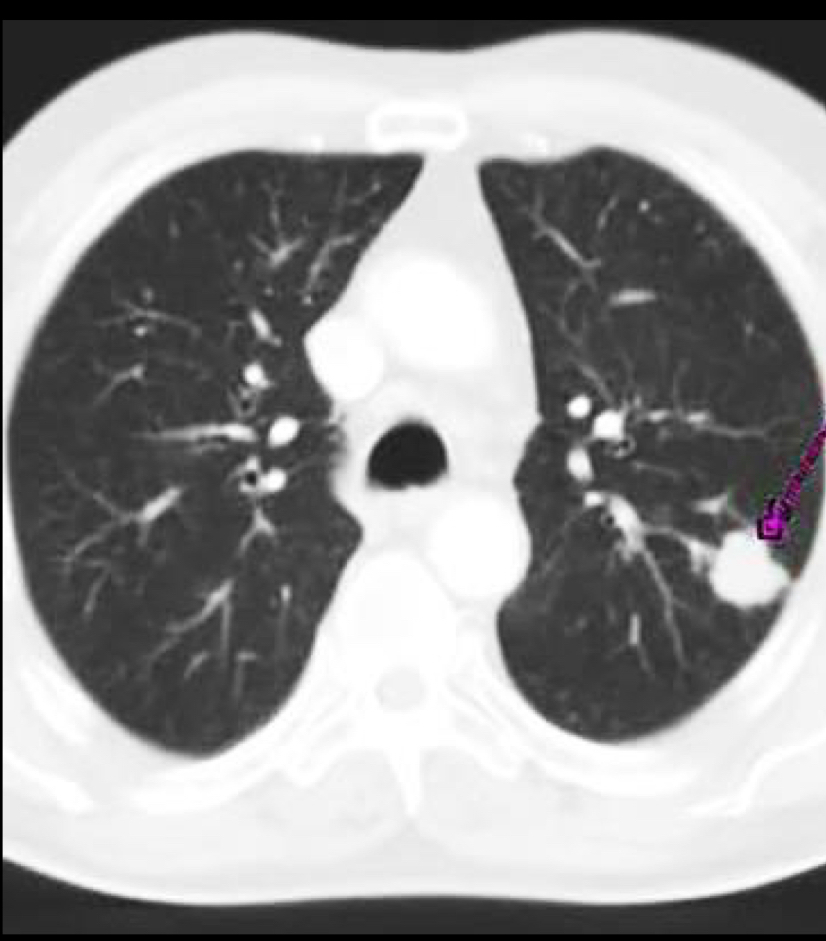

Que es?

A

Tc de ca

Nodulo 8-15 mm

se puede cavitar

SIEMPRE CON CONTRASTE